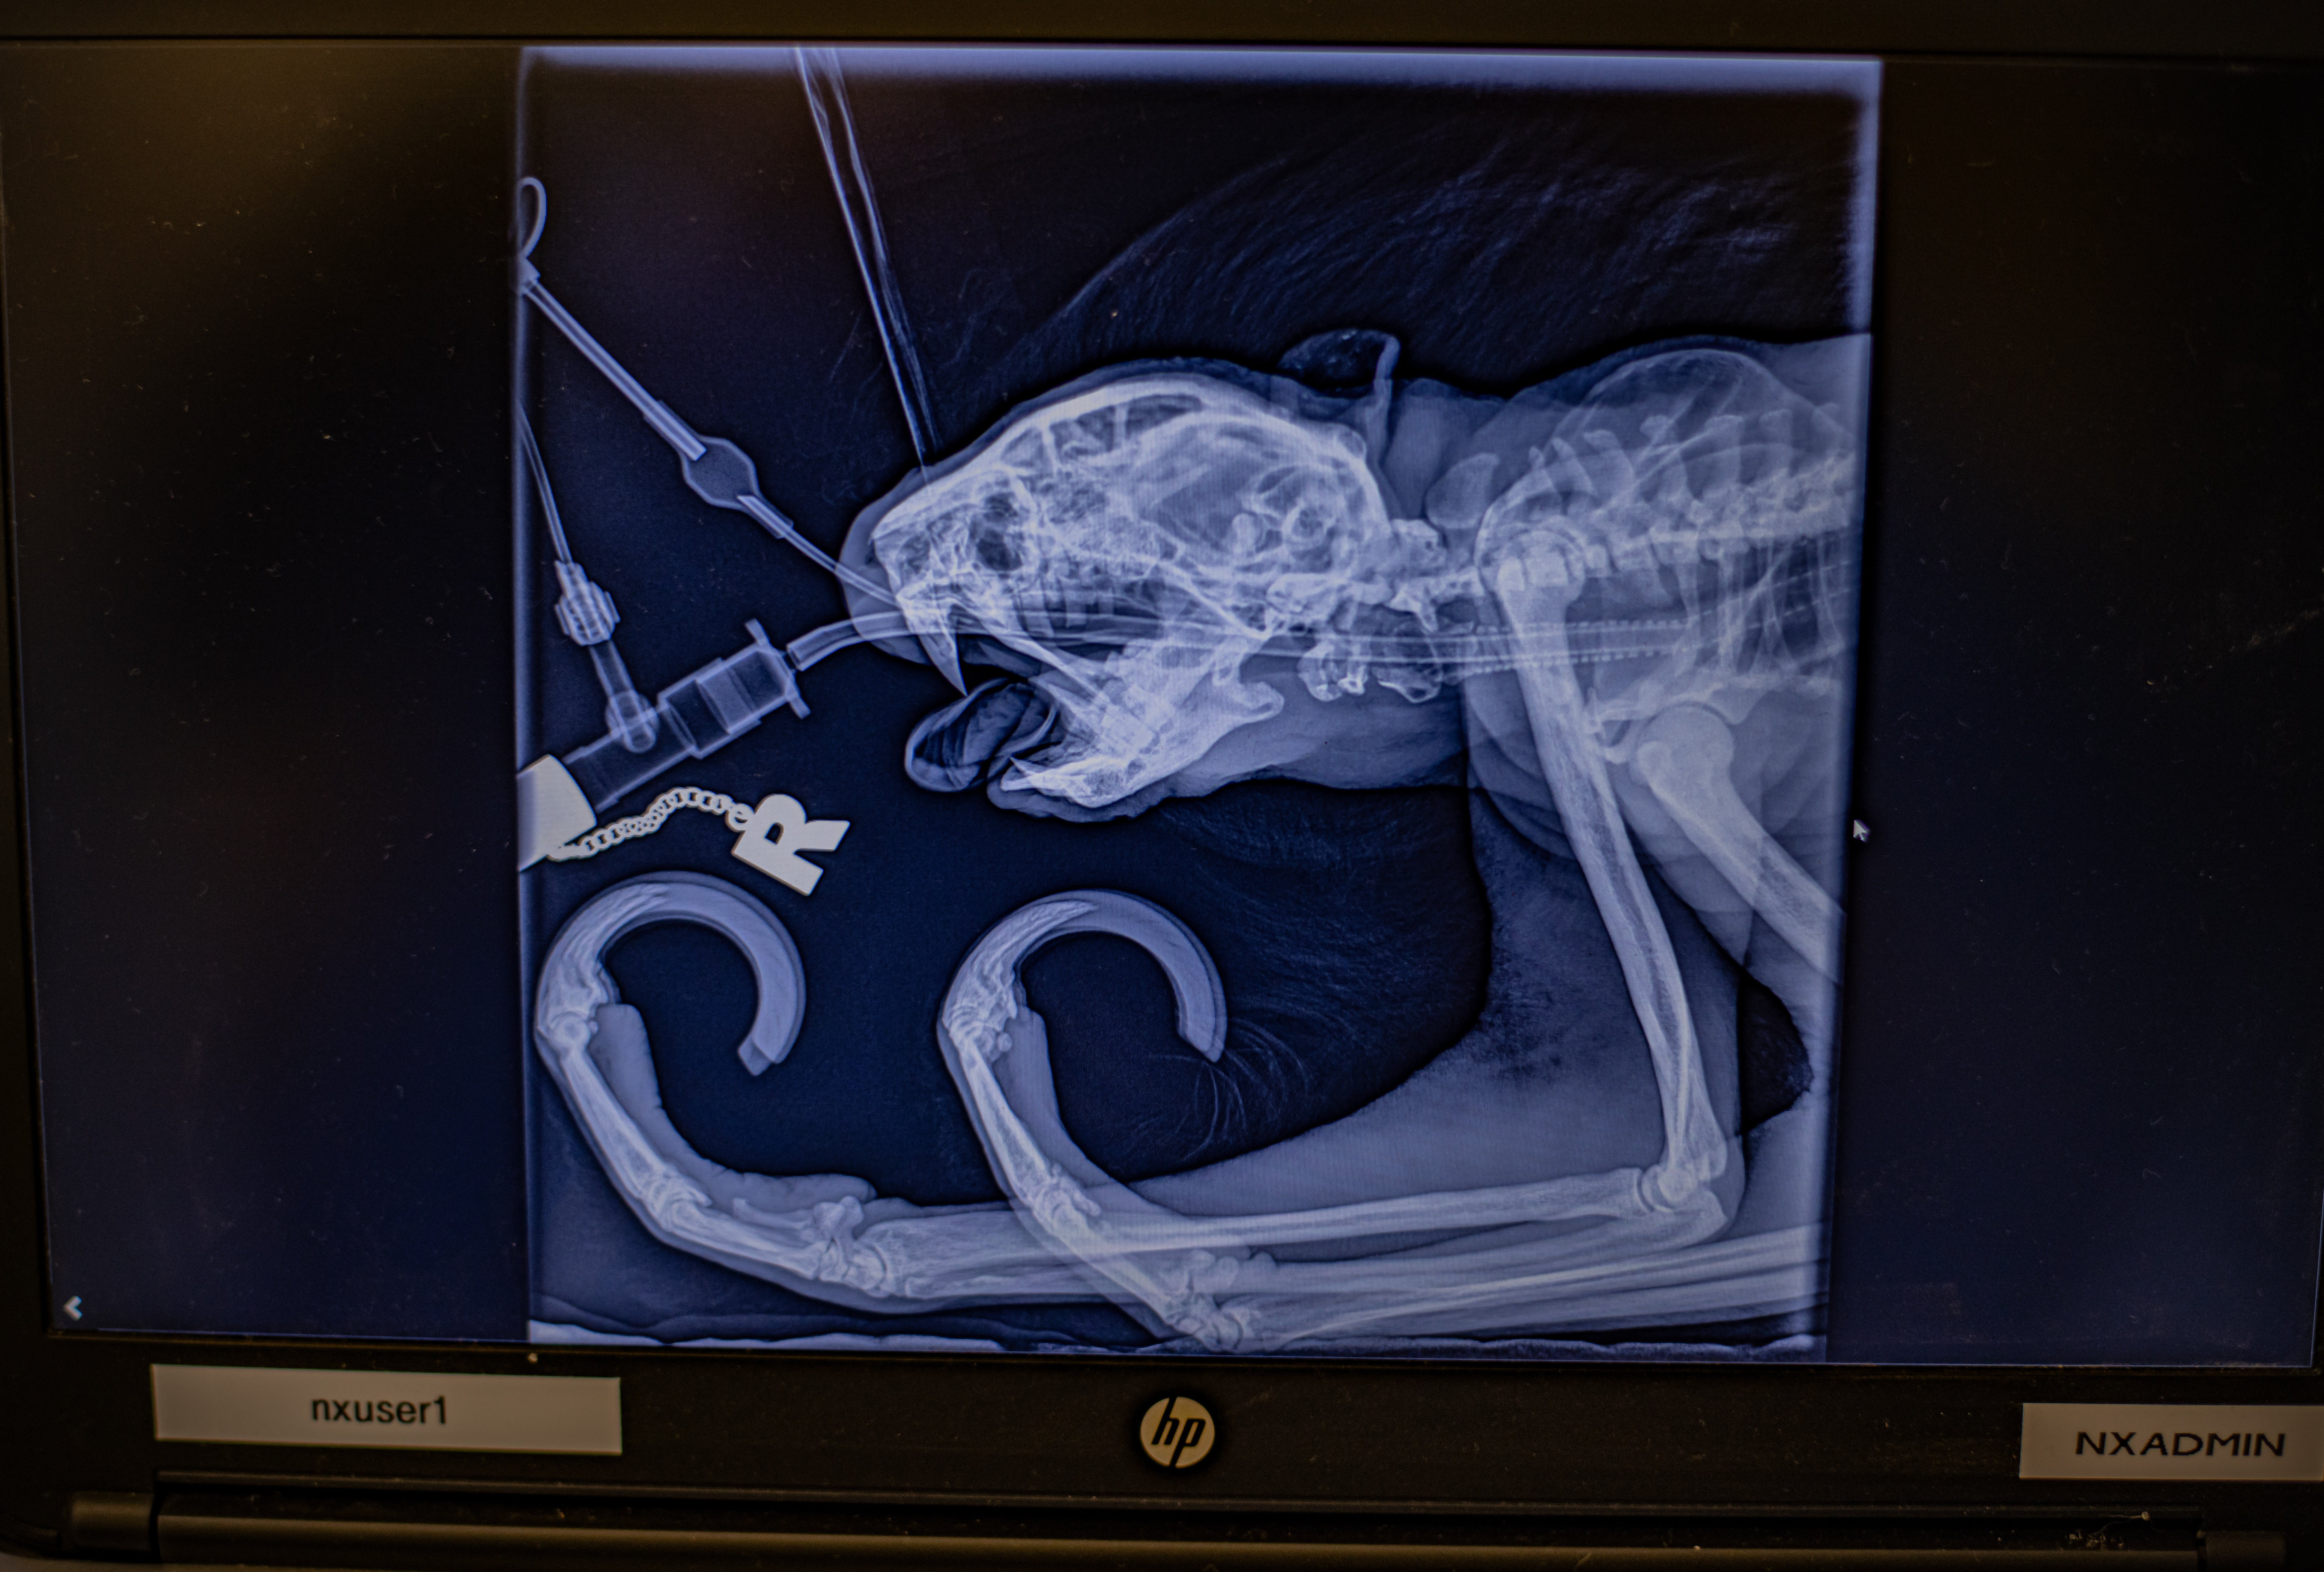

“Whilst we couldn’t save both teeth, the great news is that since his procedure, the abscesses have not come back, and his latest x-ray shows his filling is still in place. It’s safe to say that the treatment worked at treating his toothache.”

The team had to persuade Rico to position himself for an X-ray using gentle training techniques where possible, to avoid repeat anaesthetics for routine procedures.